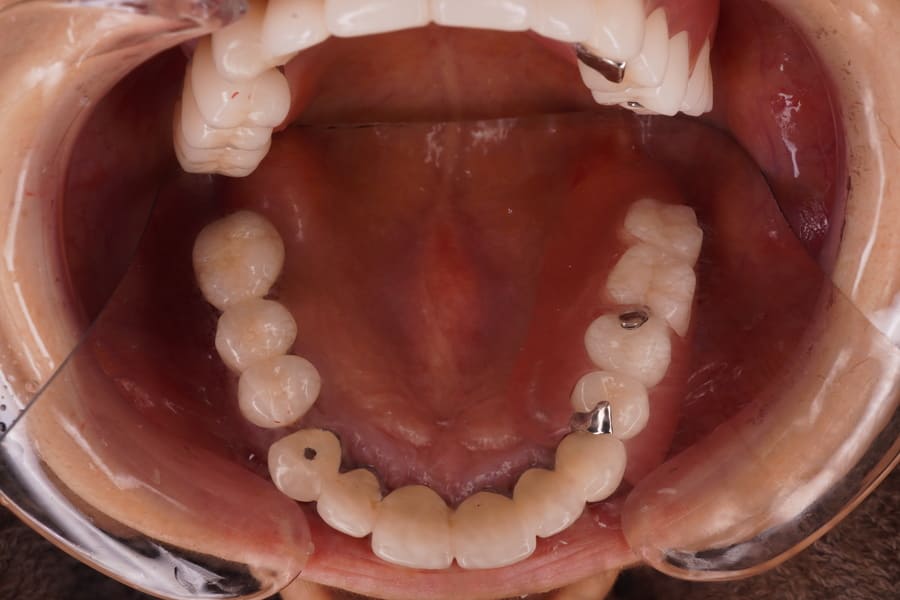

After

左上6、7番欠損。 昔、入れ歯を作ったが近年使用していない。 左上6,7番欠損の顎堤の状態は骨、粘膜とも良好。 歯周組織は最大ポケット2㎜でエックス線所見においても問題となる骨欠損は認められず4,5番とも支台歯として適応可能と判断した。 補綴装置として義歯、インプラントいずれも適応可能であった。 各種補綴方法の利点・欠点・特徴・金額を説明した後、 患者さんの希望として、出来るだけ違和感がない物、見た目もあまり金属等で目立たないもの、落としても壊れにくい物であった。 これらのことを総合的に検討して、ノンメタルクラスプデンチャーの適応を提案し了解が得られたので製作することとした。 各種あるノンメタルクラスプデンチャーの材料の種類として、耐衝撃性が高く、透明感があり適合精度に優れたポリカーボネート系を選択した。 左上4番近心、5番遠心に明瞭なレストシートを設定することとした。 日本補綴歯科学会発行のノンメタルクラスプデンチャーガイドラインにもメタルレストの重要性が述べられている。 口腔内にて冠の一部を切削・研磨して明瞭な広さ、深さのレストシートを設置した。 印象採得、咬合採得を行った。 ろう義歯試適を行い咬合のずれ等問題がないことを確認した、 患者さんに鏡を見ながら着脱の練習をしていただき、ご自身での取り扱いが可能であることを確認した。 義歯の取り扱いや管理方法について説明を行った。 1か月後にリコールを行い問題がないことを確認した。 ノンメタルクラスプデンチャーによる欠損補綴 |

| 治療期間・回数 | 治療期間17日で2回来院。 術前(2026年2月)術後(2026年3月) |